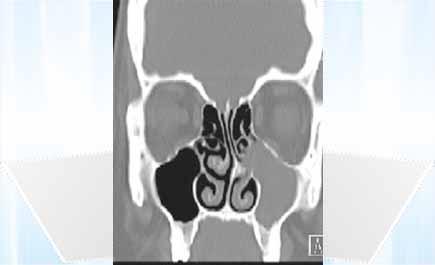

شهد المجمع الطبي بالعليا التابع لمجموعة د. سليمان الحبيب جراحة كبرى شملت عملية تجميل تشوّه خارجي بالأنف وإصلاح الحاجز الأنفي واستئصال جزئي للقرنيات السفلية والمتوسطة (Concha Bullosa) لمريضة تبلغ من العمر 36 عاماً كانت تعاني منذ سنوات طويلة من التهاب جيوب أنفية وصداع مزمن مع انسداد شديد بالأنف. هذا ما ذكرته الدكتورة لمى ياسين استشارية الأنف والأذن والحنجرة الحاصلة على البورد العربي في أمراض الرأس والعنق وجراحتها.

والتي قالت إنه بعد إجراء الفحص السريري والفحوصات الإشعاعية بالتصوير المقطعي المحوري (C.T Scan) تبيَّن وجود التهاب مزمن وشامل في الجيوب الأنفية وميلان الحاجز الأنفي وضخامة القرنيات الأنفية السفلية والمتوسطة التي تغلق فتحات الجيوب الأنفية وتسبب هذا الالتهاب وما يرافقه من صداع قوي للمريضة وانسداد قوي وشخير. وعن تفاصيل الجراحة قالت د. لمى: «العملية تم إجراؤها بالمنظار الأنفي مستغرقةً ثلاث ساعات تم فيها فتح الجيوب الأنفية وتنظيفها بالكامل مع تعديل الحاجز الأنفي علاوة على تجميل الأنف الخارجي مع استئصال جزئي للقرنيات السفلية والمتوسطة».